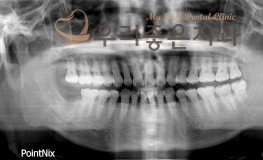

우리좋은치과 치아 상실로 인한 임플란트 보철 치료 (김** 21.05.12 ~21...

No.164

임플란트

2021-12-07

1588